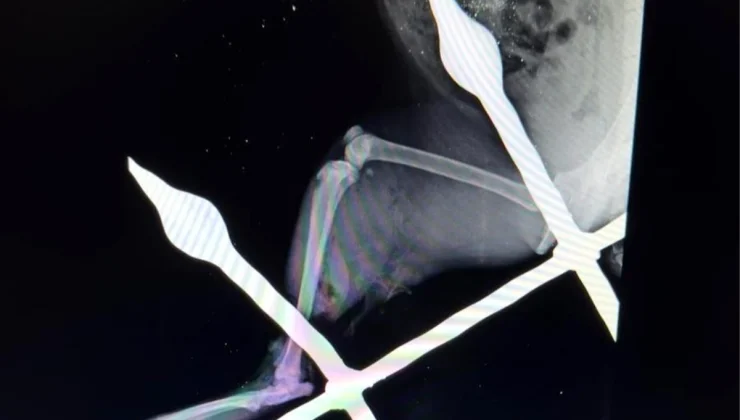

“Can dostlarımıza gerekli tüm ilgiyi gösteriyoruz”

Yaralı kedinin bacağını eski sağlığına kavuşturduklarını anlatan Mersin Büyükşehir Belediyesi Tarımsal Hizmetler Dairesinde Veteriner Hekim olarak görev yapan Yusuf İncir, “Yapılan ilk tespitler sonucunda, balkon demirinin bacağından yaklaşık 10-15 santimetre civarında geçtiği görülmüştür. Yapılan dezenfeksiyon ve temizlik işlemlerinin ardından, balkon demiri anestezi altındaki kedinin bacağından çıkarıldı. Çıkarılırken dokuya mümkün olduğu kadar zarar vermemeye dikkat ettik. Yaptığımız tespitlerde kaslardan bir tanesinin kopmuş olduğu, yalnız sinir dokusunda herhangi bir hasar oluşmadığı tespit edilmiştir. Yapılan yara temizliği ve dezenfeksiyonun ardından, kopan kas kısmı dikişle tekrar eski haline getirildi. Dezenfeksiyonun ardından, yırtılan ve hasar gören dokuların dikiş işlemini gerçekleştirdikten sonra, deri dikişi ile işlemimizi tamamladık. 12 gün zarfında kedimiz sağlığına kavuştu” ifadelerine yer verdi.